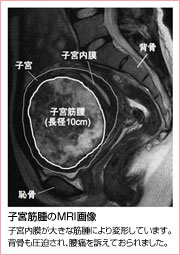

まず内診で子宮の大きさや可動性、痛みの有無をみます。そして超音波検査で腫瘍の性状を診断します。治療が必要な筋腫の場合にはMRIでさらに細かく診断していきます。貧血の有無や子宮癌との鑑別のため、血液検査や子宮癌検診も行います。